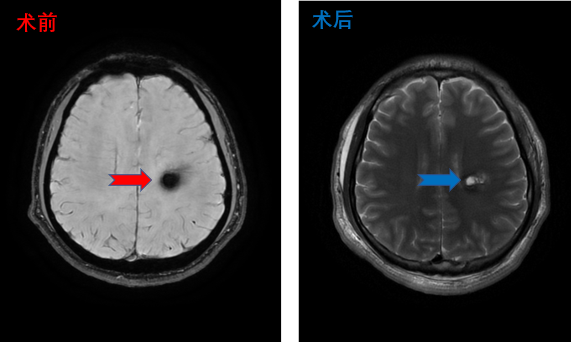

功能区低级别胶质瘤患者影像,采用术中核磁,确认肿瘤全切,术后患者左下肢肌力Ⅳ级